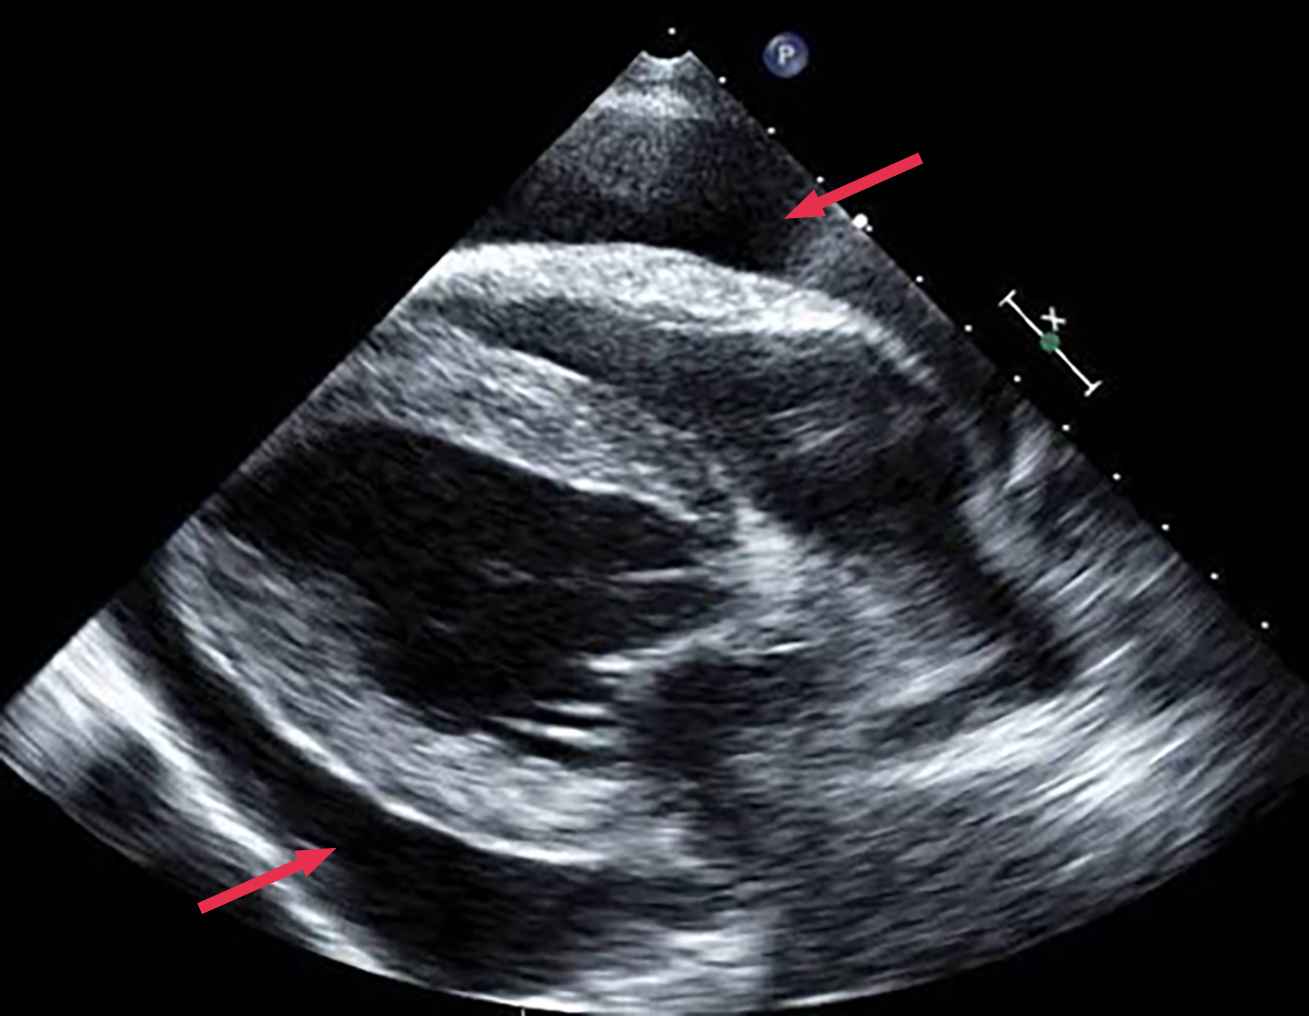

Une échographie POCUS (Point Of Care UltraSound) thoracique confirme la présence d'un épanchement péricardique (photo n° 2).

L'état de choc observé (faiblesse, tachycardie, muqueuses pâles, TRC prolongé, hypothermie) est attribuable à une tamponnade cardiaque induite par l'épanchement péricardique, responsable d'un choc obstructif.

Dans ce cas, l'échocardiographie n'a pas montré d'anomalie, laissant suspecter un épanchement péricardique idiopathique.